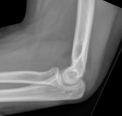

Findings may be quite subtle and the only clue may be the fat pad sign (triangular radiolucent shadows anterior and posterior to the distal humerus on lateral X-ray, indicating haemarthrosis and displacement of intra-articular fat pad - often associated with intra-articular skeletal injury).

Image of elbow fat pad sign (Hellerhoff (own work), via Wikimedia Commons):

Elbow fat pad sign

James Heilman, MD, CC BY-SA 4.0, via Wikimedia Commons